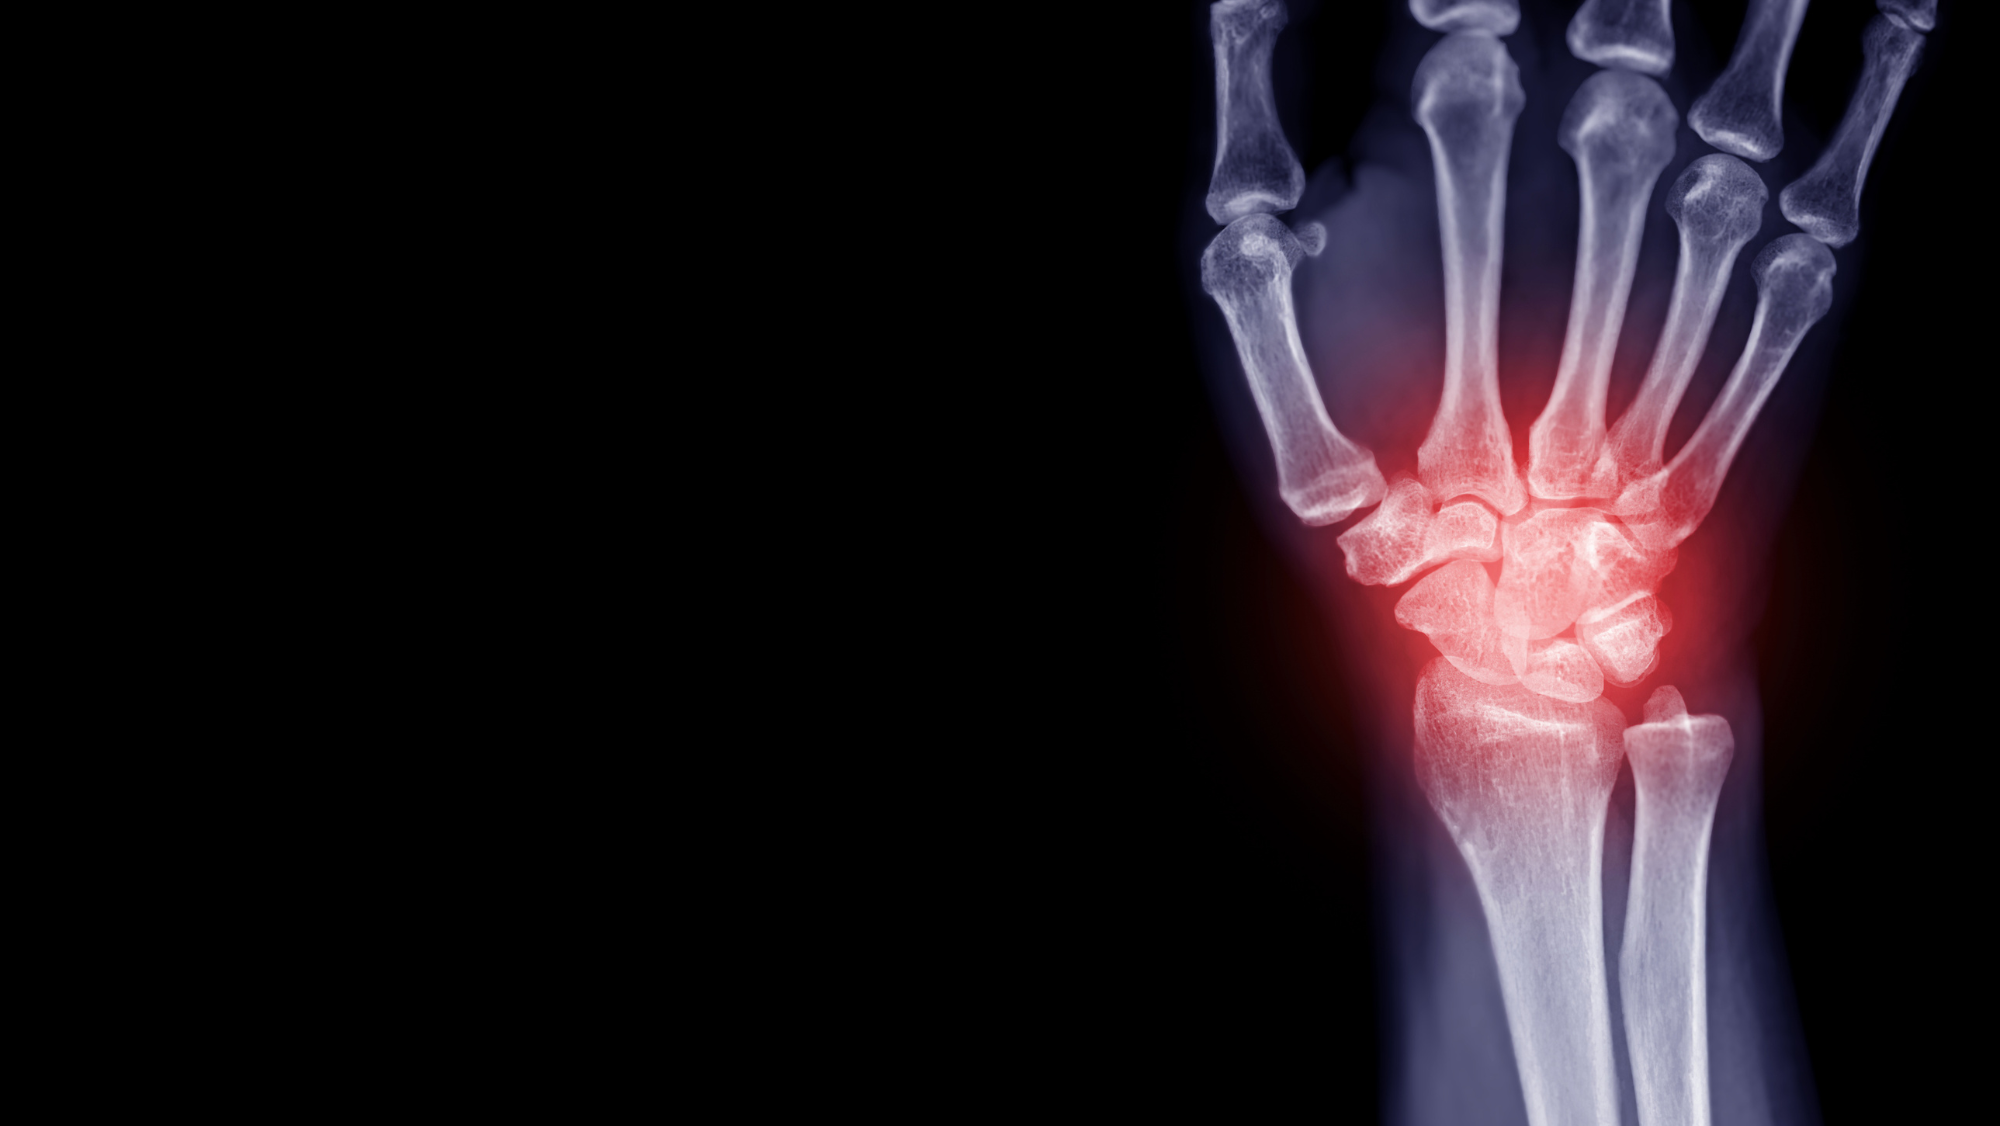

There are a number of methods through which CBD might assist with joint ache. One of many major methods is thru its anti-inflammatory properties. Irritation is a serious contributor to joint ache, and CBD has been proven to cut back irritation within the physique. This will help to alleviate ache and stiffness within the joints.

Analysis has proven that CBD reduces the degrees of pro-inflammatory cells within the physique, all whereas growing the degrees and effectiveness of essential immune cells. [2]

CBD has additionally been discovered to focus on the areas of the joints affected by power irritation in these with rheumatoid arthritis, offering aid. [3]